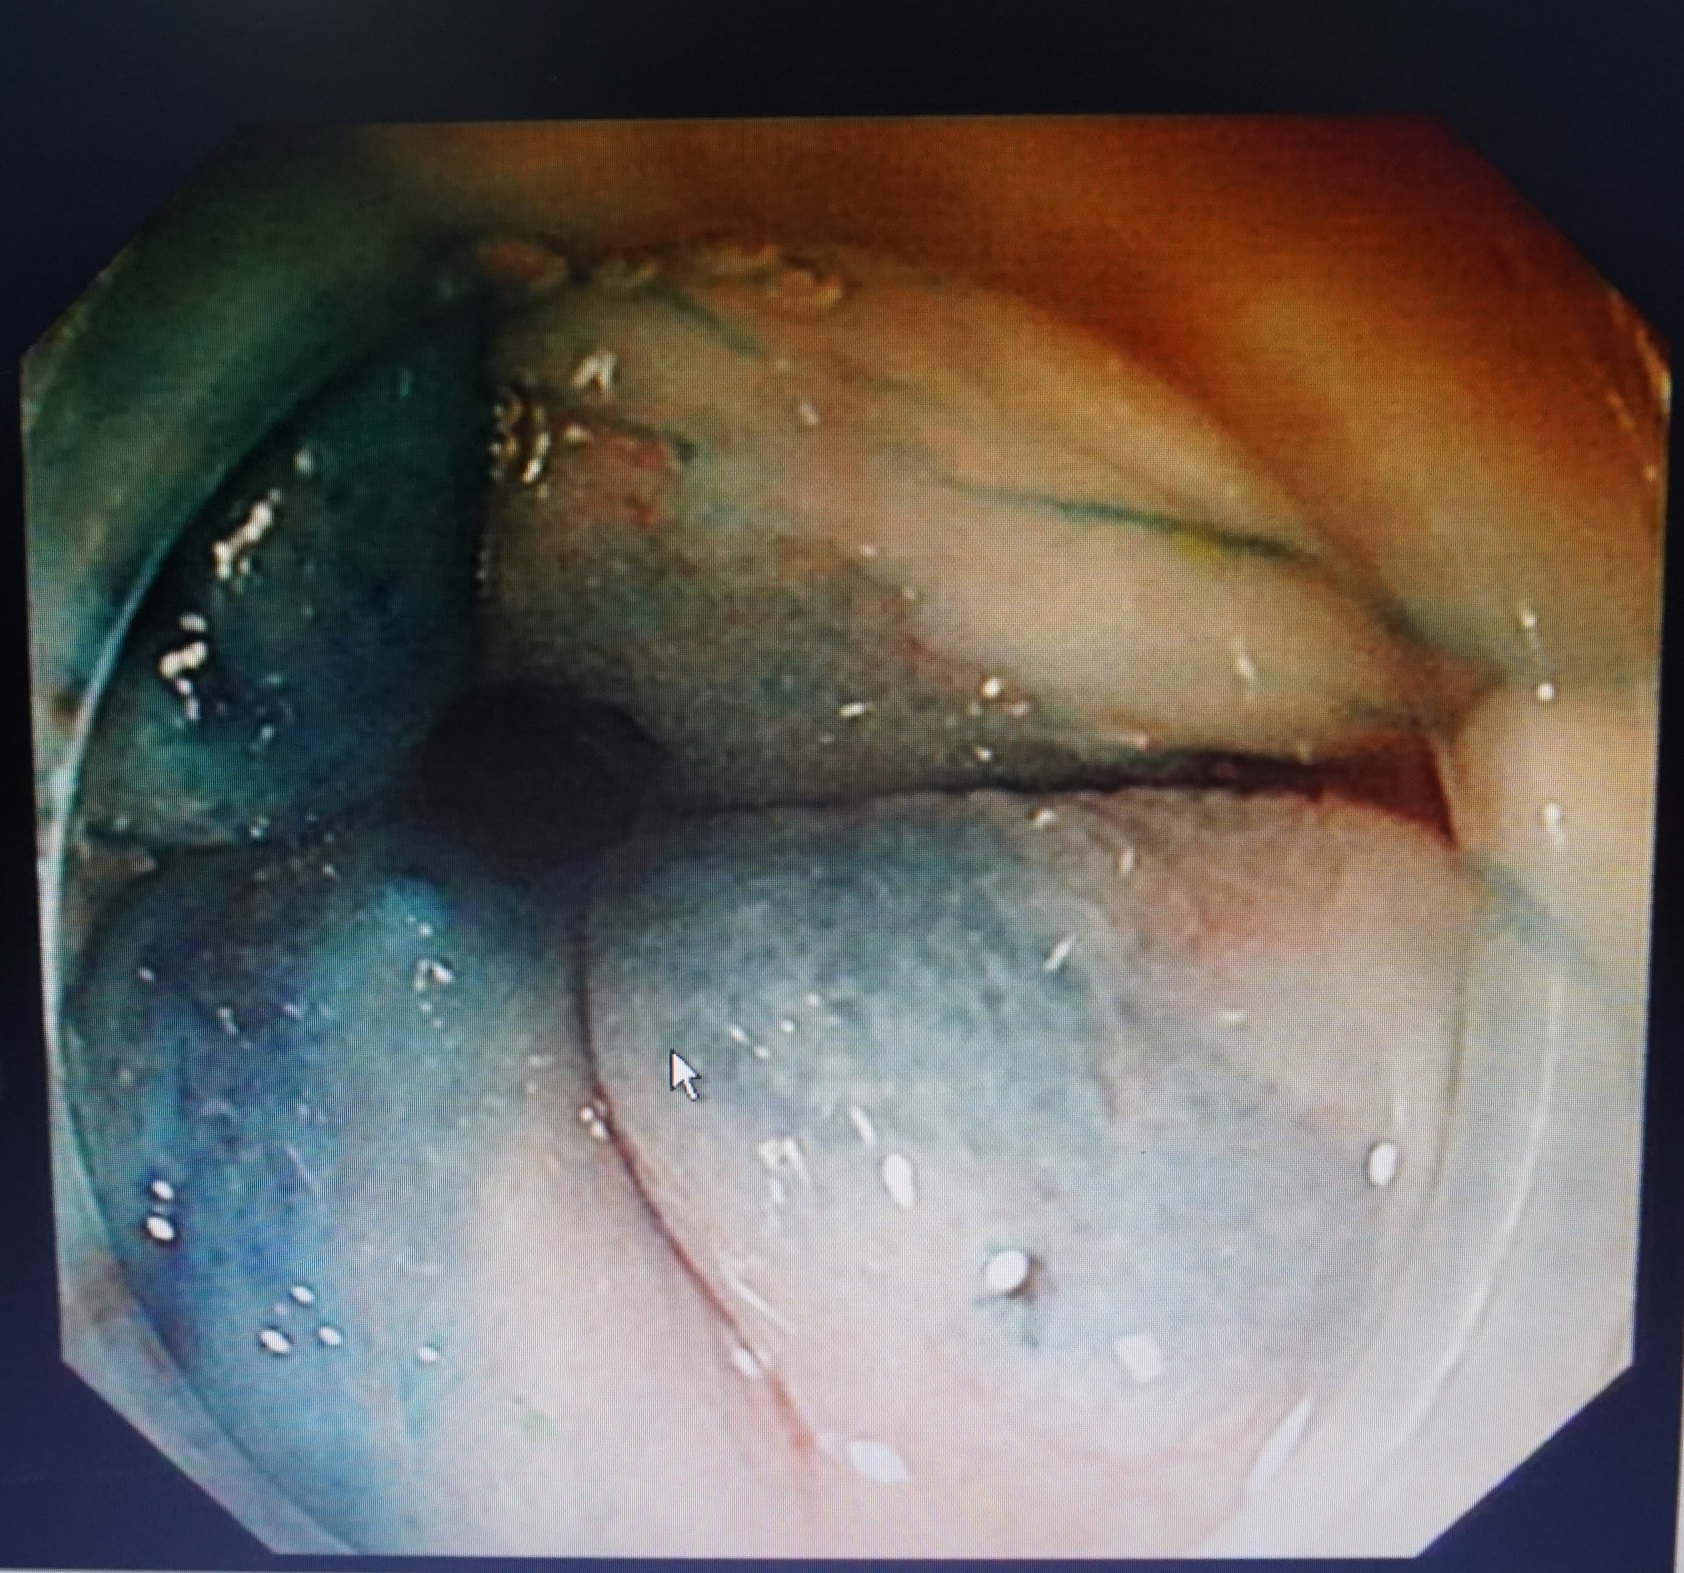

硬化剂注射治疗

我院消化科专家团队仔细研究患者病情、认真讨论后,诊断为痔疮。考虑到杨奶奶年事已高,基础疾病较多,为了减少对患者身体及体力的损害、取得较快的恢复和较好的预后效果,决定为杨奶奶行内镜下治疗。经患者及其家属同意,王军主任医师为患者实行了治疗。患者肛口见Ⅱ期内痔,排除消化道肿瘤等疾病后,用硬化剂顺时针依次每点进行注射治疗,操作过程中没有不适症状,手术后没有疼痛。第4天,杨奶奶便出院了。